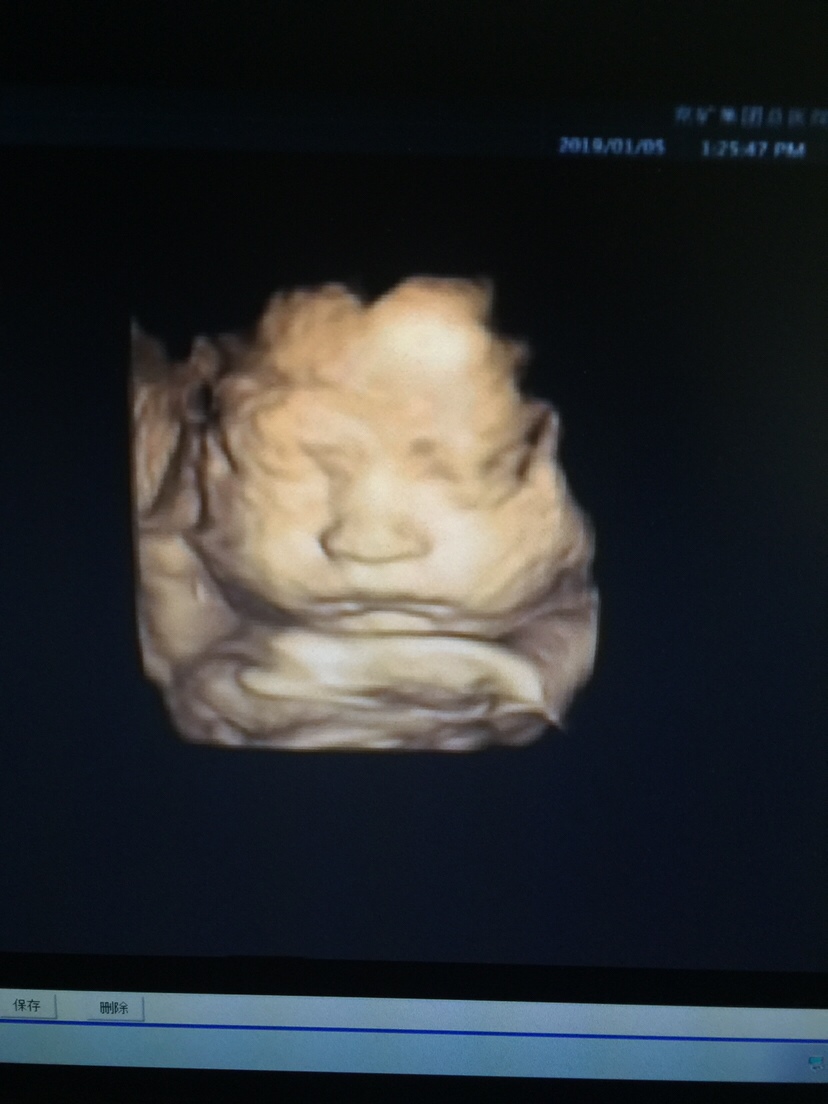

孕33周+5天

这个孩子胖嘟嘟的。好可爱